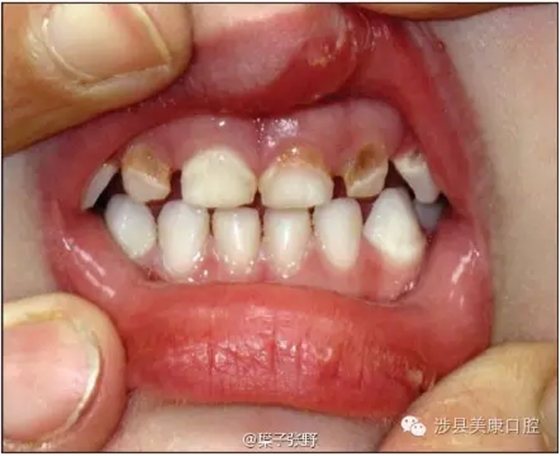

影響美觀,讓小朋友笑話。

![SGTCU9W{CJ(KNO938]DJZ[Q.png SGTCU9W{CJ(KNO938]DJZ[Q.png](/Mobile/UploadFiles/FCK/2017-04/6362664285172919675298344.png_280.jpg)

影響咬合高度建立

會(huì)感染,嚴(yán)重者可以引起全身病變,危機(jī)生命。

牙根周圍頜骨腐爛吸收。